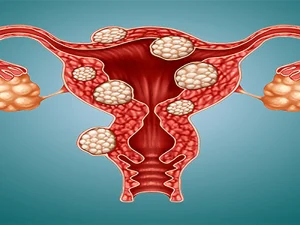

درمان اندومتریوز؛ راهنمای جامع برای انتخاب بهترین روش

درمان اندومتریوز رحم یکی از دغدغههای بیماران این بیماری است، که در بیشتر موارد این عارضه در سن باروری ایجاد میشود. که میتواند زندگی، باروری

درمان اندومتریوز رحم یکی از دغدغههای بیماران این بیماری است، که در بیشتر موارد این عارضه در سن باروری ایجاد میشود. که میتواند زندگی، باروری

فیبروم رحم یکی از شایعترین تودههای غیر سرطانی خوشخیم در میان زنان در سنین باروری است که در دیواره رحم یا اطراف آن رشد میکند.